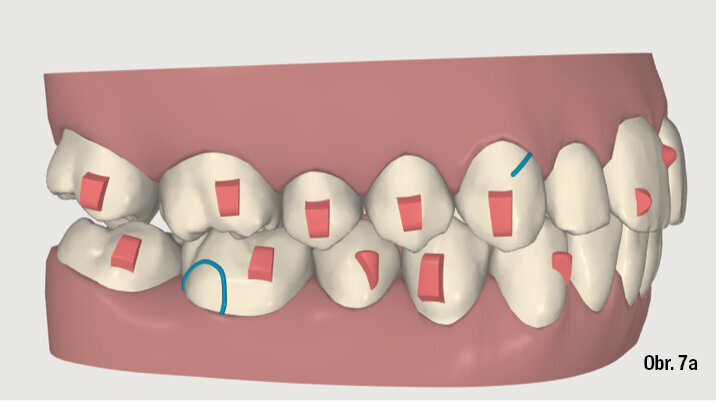

Na překrytí kefalometrických snímků je zřejmá distalizace molárů o 6 mm bez výraznějšího sklonu a s ideálním bukolingválním sklonem řezáků. Tahy druhé třídy umožnily protrakci mandibuly o 1,5 mm. Jako retenční aparáty jsme zvolili Vivera retainery (Align Technology) (obr. 6, 7a–c, 8a–c).